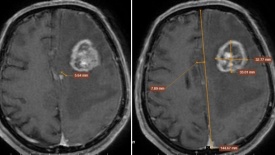

Dấu hiệu yếu tay tưởng nhẹ, người đàn ông 67 tuổi phát hiện ung thư di căn não

Những biểu hiện tưởng chừng thoáng qua như yếu tay, khó cầm nắm hay đau đầu kéo dài có thể là dấu hiệu sớm của bệnh lý nguy hiểm. Trường hợp bệnh nhân 67 tuổi tại Hà Nội là lời cảnh báo về nguy cơ bỏ lỡ “thời điểm vàng” trong phát hiện ung thư.